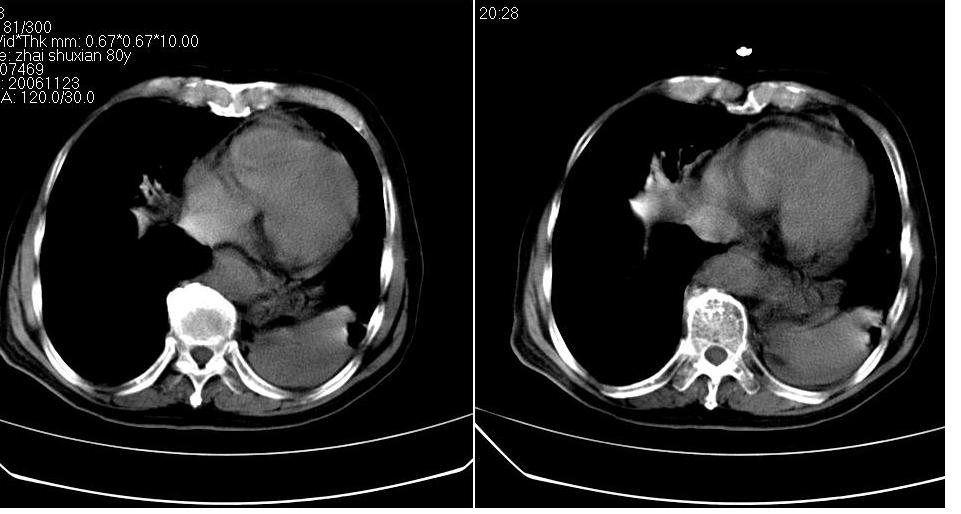

左肺下叶略萎陷、实变,内可见含气支气管征。左舌叶、中叶亦见少许斑片状高密度区,边界不清。纵隔未见肿大淋巴结影。

左下肺体积缩小,密度增高,见片增密影。边界模糊,见支气管充气像,肺门纵隔无异示,心脏气管左移,左侧胸腔少量积液。考虑肺部感染伴部分肺不张[有脑梗塞病史坠积性肺炎可能]

1、左肺下叶后基底段炎症并膨胀不全。

2、左侧胸腔积液。

左肺下叶体积缩小,成类楔形软组织影,其内可见部分含气支气管影,相应左侧肺门区未见明显肿块,考虑炎性病变,建议抗炎后短期复查

左下肺体积缩小,密度增高,并见大片状致密影,边界模糊,其内见支气管充气像,肺门纵隔无异常,心脏气管左移,左侧胸腔少量积液。考虑:左肺炎性病变伴不张。